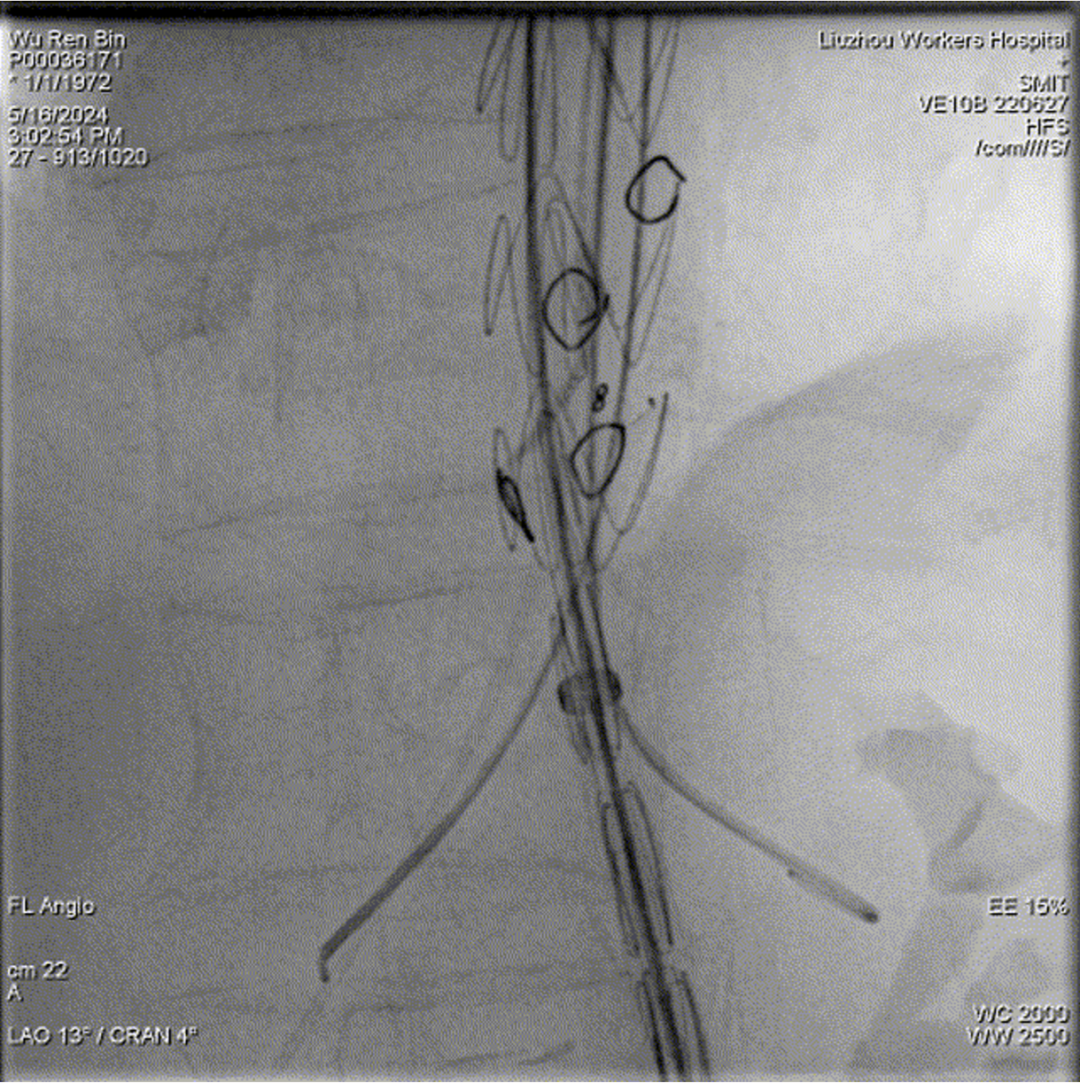

个体化标记:标记分支动脉开口,便于术中快速精准的腔内超选和置管。

以不同颜色的醒目圆圈标记双肾动脉、肠系膜上动脉、腹腔干开口

3D影像融合技术的关键步骤

影像配准:根据术中实时影像对3D影像进行必要的微调校正。

术中3D影像引导,主体支架精准定位

3D影像引导下,

主体支架窗口与弓上三分支开口对位

依次超选无名、左颈总及左锁骨下动脉